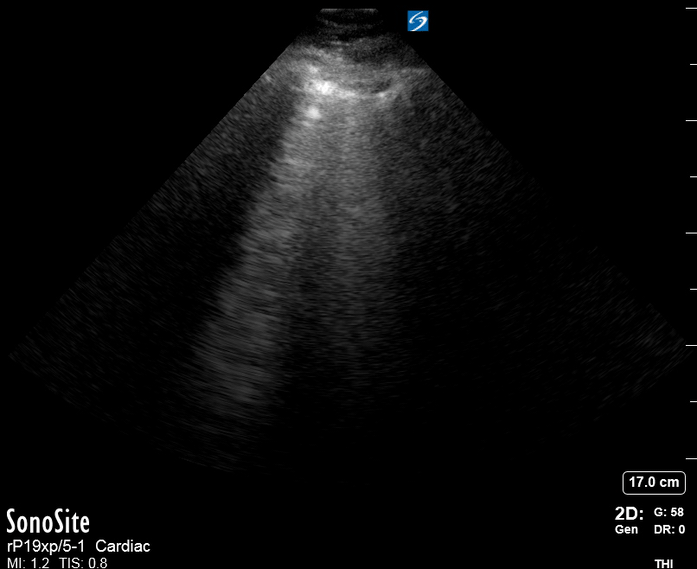

IVC exploration is best from the subxiphoid approach with longitudinal and transverse images. The IVC should be assessed in terms of overall size and collapsibility. The diameter is typically measured at its largest (end of expiration) at 1-2 cm distal to where the hepatic veins join the vena cava. An IVC diameter of ≥ 2 cm, especially with minimal or no collapsibility, is considered plethoric and correlates with increased RA pressure. An IVC of < 1 cm, particularly with complete collapse, is considered flat and indicates low preload and potential fluid responsiveness. An IVC diameter between 1 and 2 cm is typically normal.

PITFALLS

In a long-axis view, beware of not sliding off the centre of the vessel, as this will underestimate the size of the IVC and overestimate its collapse. Obtaining long and short axis views may help avoid this pitfall. Another mistake is confusing the descending aorta for the IVC, particularly when scanning in long-axis. Although the IVC may appear to pulsate, the aorta has a thicker wall, and its position is to the patient’s left. Following the IVC upwards will reveal the hepatic veins junction and the entrance to the RA, while the aorta will travel behind the heart. The IVC moves both anterolaterally and craniocaudally with inspiration, and this should be considered during visualization or measuring. For this very reason, measuring in M-mode is not recommended as it would not be accurate.